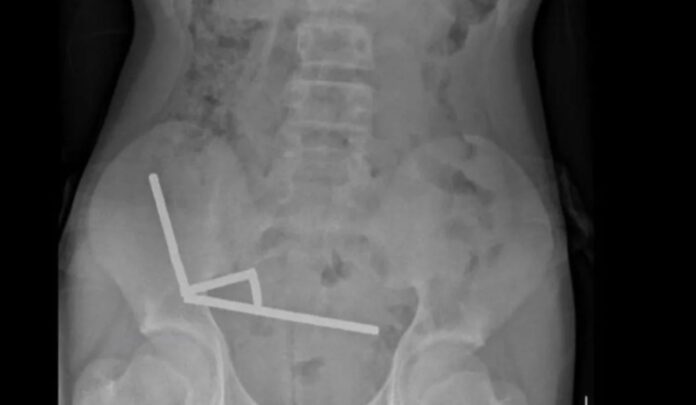

O material havia se agrupado em quatro correntes no abdômen, conectando diferentes partes do intestino. A atração magnética resultou em uma necrose por pressão no órgão, exigindo uma cirurgia de emergência.

Ao longo do procedimento, os ímãs foram retirados, mas parte do intestino delgado e grosso precisou ser removida. O menino ficou oito dias hospitalizado até receber alta.